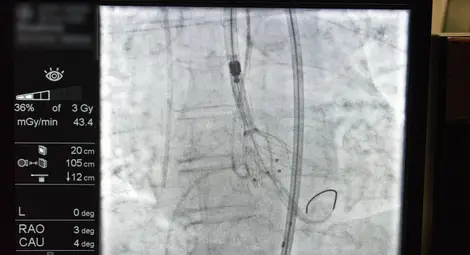

От общо четирите демонстрации на живо, излъчвани с двупосочна аудио-видео връзка, три бяха осъществени от русенските медици – признание за високата класа на операторите и на кардиологичната клиника. От ангиозалите на МЕДИКА водещият интервенционален кардиолог и медицински директор на кардиологичната болница проф. Добрин Василев демонстрира две ендоваскуларни процедури. Първата беше транскатетърно имплантиране на аортна клапа (TAVI) при пациент с високостепенна аортна стеноза – минималноинвазивна техника, която елиминира необходимостта от отваряне на гръдния кош и значително намалява риска от усложнения. Втората интервенция, представена от професора, беше орбитална атеректомия – съвременен метод за обработка на силно калцирани артериални плаки. МЕДИКА е сред утвърдените центрове в региона, които рутинно прилагат тази техника и я демонстрираха пред своите сръбски колеги, за които тя все още не е част от ежедневната практика.

Демонстрация на живо направи и още един представител на русенското лечебно заведение, този път от ангиозалата на Кардиологичната болница в Зайчар. Интервенционалният кардиолог д-р Октай Максудов извърши комплексна периферна реваскуларизация (PTCA) на двата долни крайника на пациент. Модерната минималноинвазивна процедура е рутинна практика в Сърдечно-съдовия център на МЕДИКА, а д-р Максудов в последните години активно помага на сръбските си колеги в усвояването на този вид интервенции. Освен това русенският специалист е сред най-ангажираните организатори на симпозиума.